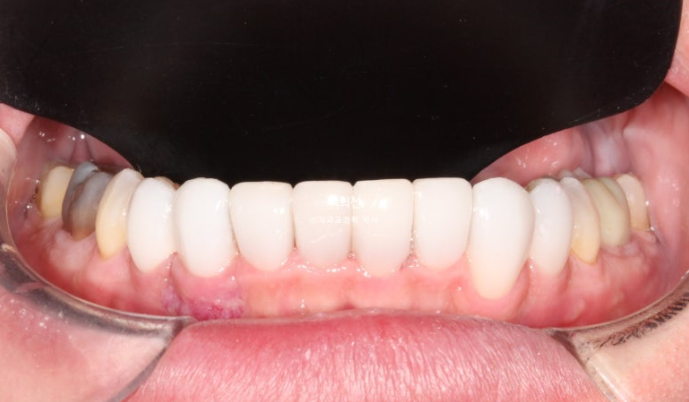

This is what the Gelami looks like on the 8 lower front teeth.

This is an occlusal surface photo that gives an idea of the thickness of Gelami.